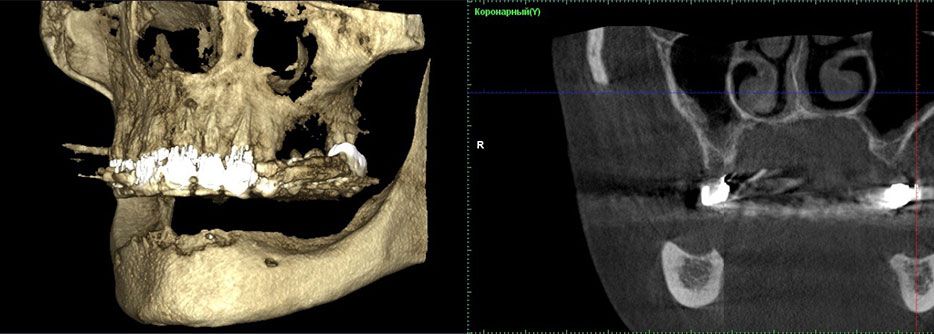

Щоб визначити можливість виготовлення постійної ортопедичної конструкції, що спирається на дентальні імплантати, була проведена комп'ютерна томографія (мал.1).

Мал. 1. Комп'ютерна томографія бічній ділянці нижньої щелепи до лікування

Дослідження показало, що у пацієнта є кісткова тканина типу I відповідно до класифікації Lekholm і Zarb.

Бічні ділянки, де були вставлені імплантати, альвеолярного гребеня мали ширину 10,63 мм і висоту 12,60 мм. Відстань між кортикальної платівкою і нижньощелепним каналом склало всього 4,84 мм.